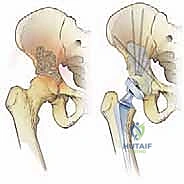

استبدال مفصل الورك الكلي لآفات السرطان النقيلي هو إجراء جراحي معقد يهدف إلى تخفيف الألم واستعادة وظيفة المفصل وتحسين جودة حياة مرضى السرطان. يتضمن إزالة الأنسجة العظمية المتضررة واستبدالها بمفصل اصطناعي لضمان تثبيت قوي ودائم.

يُعد تشخيص السرطان في حد ذاته تحديًا نفسيًا وجسديًا هائلاً، ولكن عندما يتطور المرض وينتشر إلى العظام (ما يُعرف بالنقائل العظمية)، وتحديداً إلى منطقة مفصل الورك وعظم الفخذ، فإنه يضيف طبقة قاسية من التعقيد والألم المبرح لحياة المريض. تهدف جراحة استبدال مفصل الورك الكلي (Total Hip Arthroplasty - THA) في حالات الآفات السرطانية النقيليّة إلى تقديم حل جذري لتخفيف هذا الألم الشديد، استعادة القدرة على الحركة المستقلة، وتحسين جودة حياة المريض بشكل عام في مرحلة حرجة من حياته.

إن هذه الجراحة ليست مجرد عملية استبدال روتينية للمفصل كما يحدث في حالات الخشونة أو الاحتكاك العادي؛ بل هي تدخل جراحي دقيق للغاية يتطلب خبرة عميقة، تخطيطًا استثنائيًا، وفهماً دقيقاً للميكانيكا الحيوية للتعامل مع العظام المتضررة والمخاطر المحتملة مثل النزيف أو عدم استقرار المفصل.